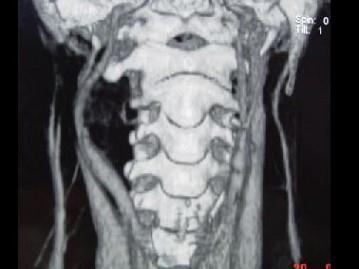

问题 男,41岁,右侧咽部不适两年余,有异物感,声音嘶哑,CT如图所示,最可能诊断为 ( )

选项 A、小唾液腺瘤 B、咽旁神经鞘膜瘤 C、咽旁转移癌 D、咽旁淋巴瘤 E、颈动脉体瘤

答案 B